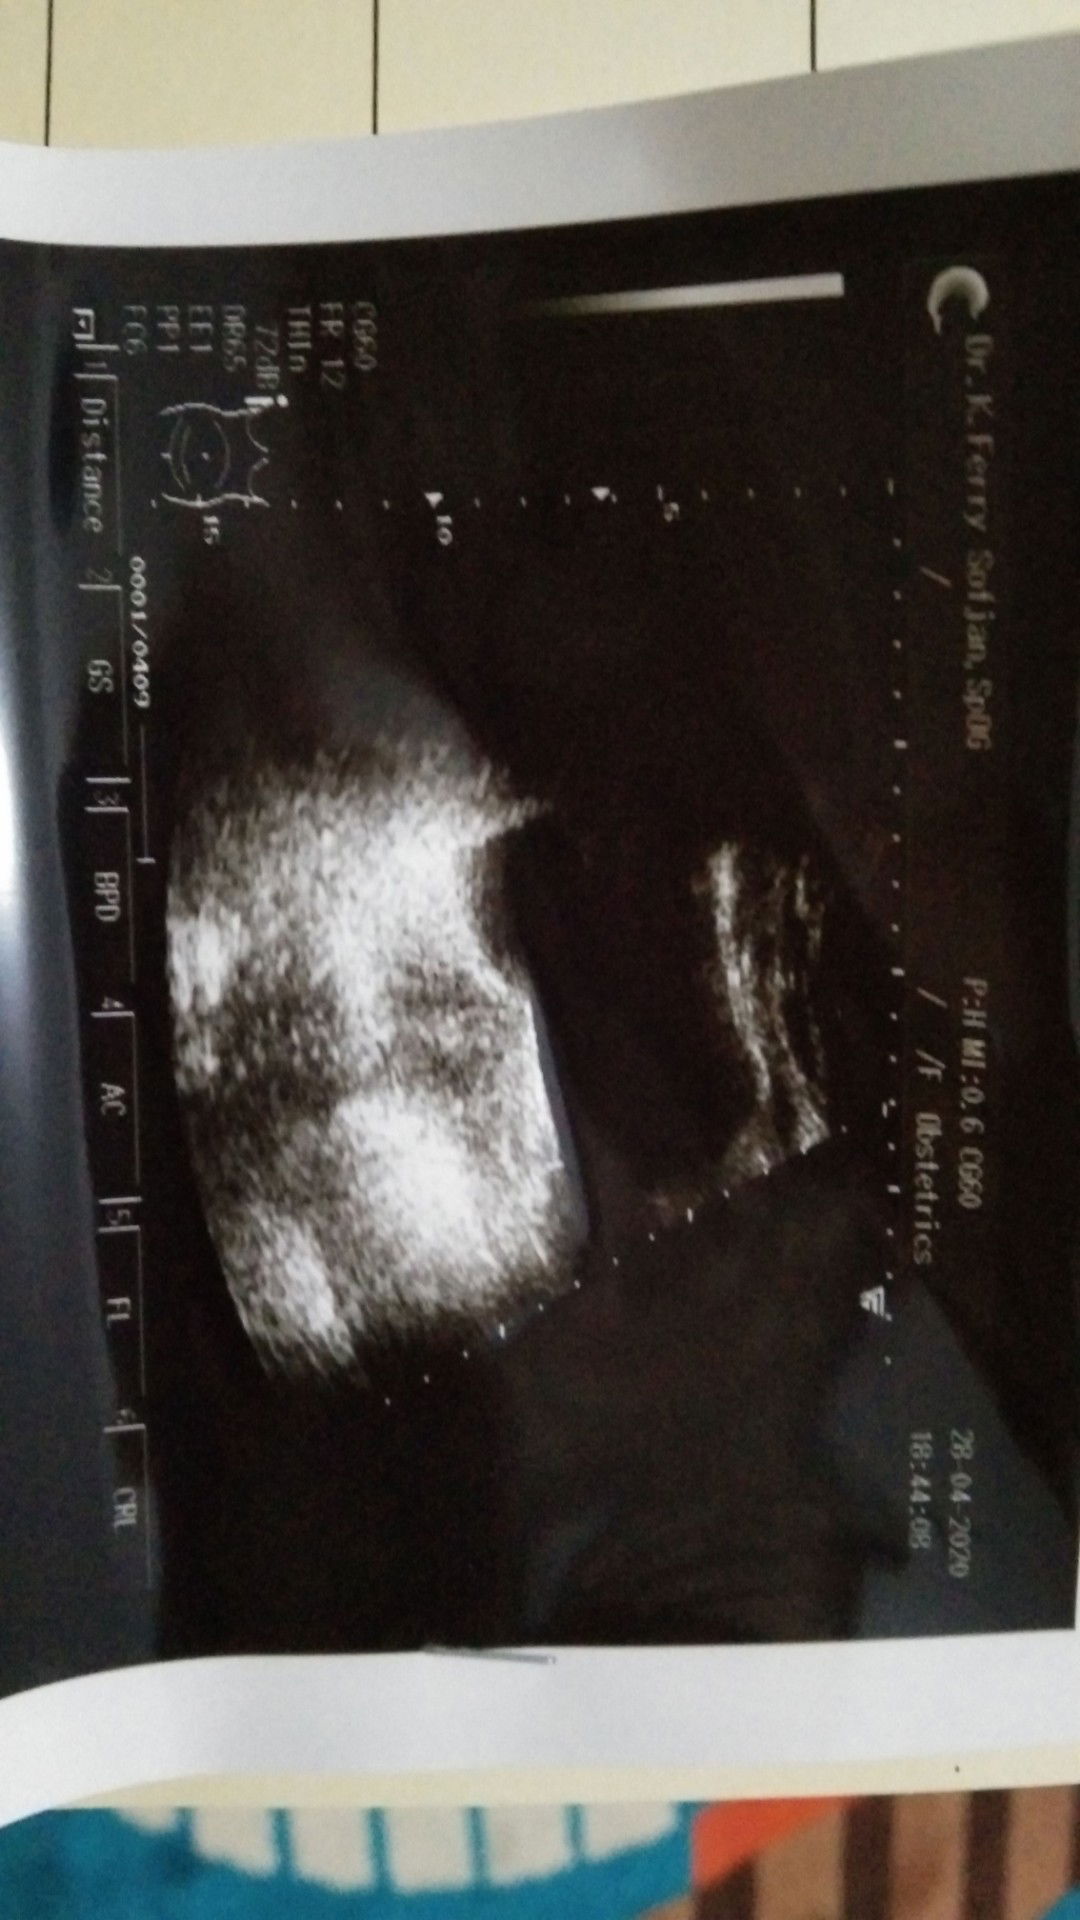

usg pertama saat tau positif (lagi)

Bun ada yg bisa baca usg ?

Hallo bunda , disini pengalaman yg pernah kuret gmn bun ? Saya sudah usg transv. Akhirnya sya di nyatakan BO . sedihhh rasa nyaaa sakit hati . tolong share dong bunda yg pernah BO dan harus kuretase

usg transV

Assalamualaikum bunda ,disini ada ga ya yg pengalaman usg di 10w tp belum keliatan janin nya , da usia kandungan di usg tryata baru 7w3D. Sedangkan bidan hitung dr hpht itu usia 10w . jujur saya bingung harus gmn lg. Plg usg panik sampe nangis sepanjang jalan , ditambah dokter ngomong gini "duh belum keliatan mba janin nya baru kliatan kantung janin nya aja ,saya jg belum bisa mastiin kalo ini hamil kosong ,nanti balik lagi 2 minggu lg ya" . dan yg jd pertanyaan , saya udh ga haid selama 2 bulan jg , tp usia kdungan saya saat usg baru 7 minggu, ditambah dokter ngomong gitu . bunda bunda yg sudah berpengalaman tolong share dong apa yg harus saya lakukan . terimakasih